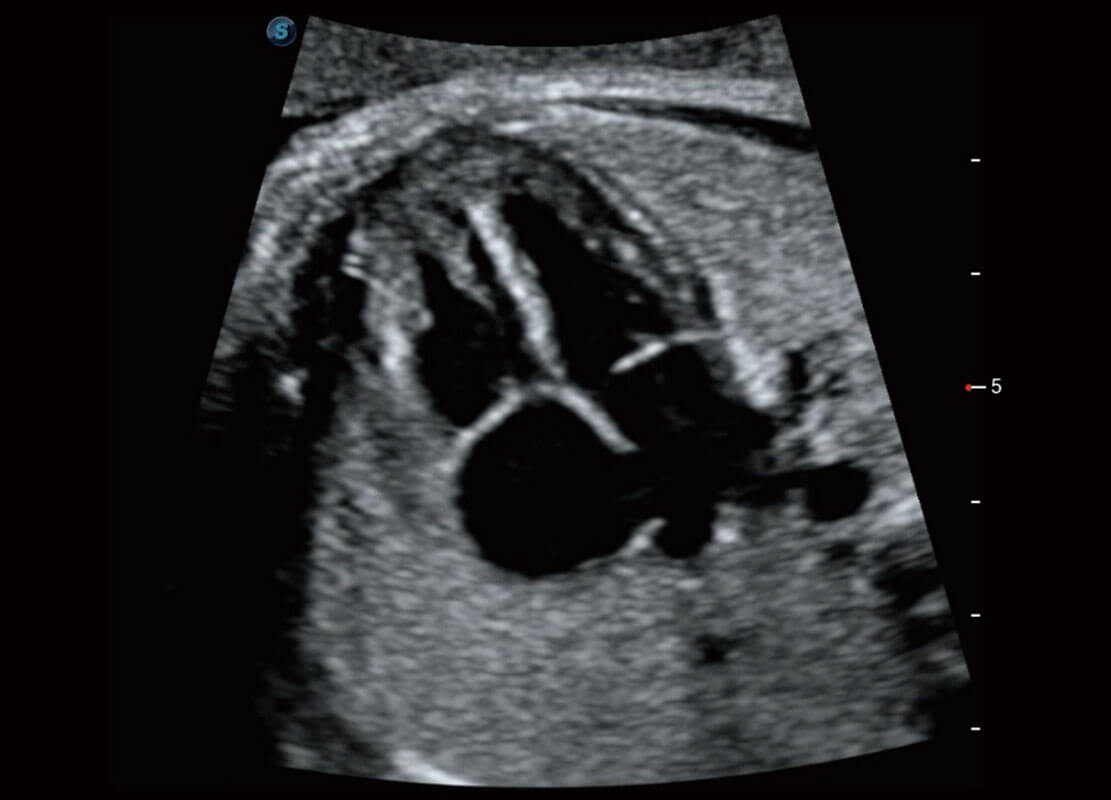

P60搭載寬頻帶線(xiàn)陣探頭、寬景成像、彈性成像技術(shù),為您提供乳腺應(yīng)用方案。P60支持高頻相控陣探頭、線(xiàn)陣探頭、腹部高頻探頭、腹部微凸探頭等,豐富的探頭群搭載敏感的彩色血流成像,適用于新生兒多種臟器檢測(cè)要求,滿(mǎn)足新生兒篩查需求。

新生兒心臟